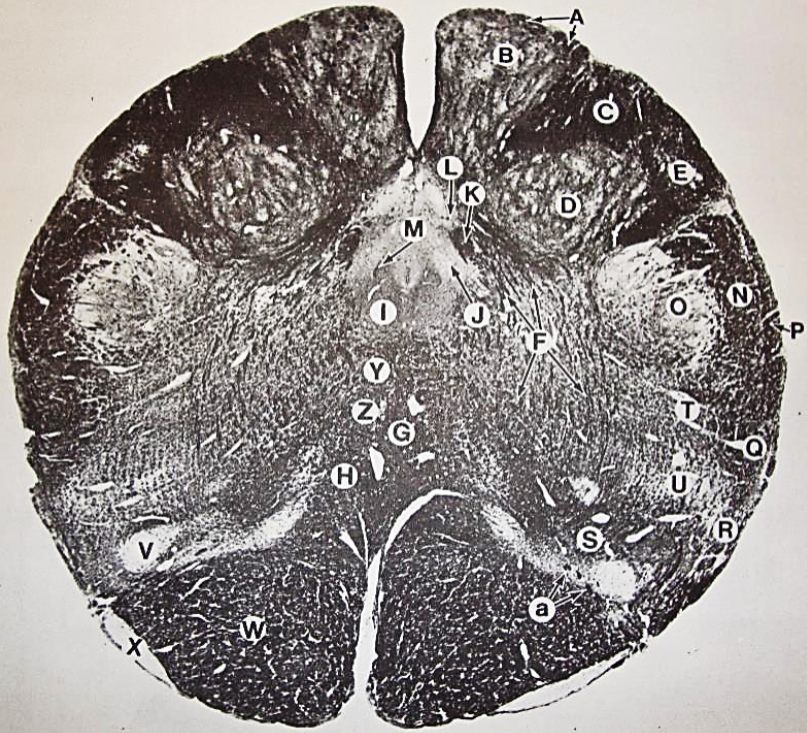

A

Lateral Cuneate nucleus

B

dorsal external arcuate fibers

C + D collectively

vestibular nuclei

C + D collectively

vestibular nuclei

E

dorsal motor nucleus of vagus nerve

F

solitary fasciculus

G

solitary nucleus

H

nucleus ambiguous

I

fascicles of glossopharyngeal nerve

J

hypoglossal nucleus

K

fascicles of hypoglossal nerve

L

dorsal longitudinal fasciculus

M

central tegmental tract

N

inferior olivary nucleus

R

inferior cerebellar peduncle

S

spinal trigeminal tract

T

spinal trigeminal nucleus

U

ventral trigeminothalamic tract

V

pyramidal (corticospinal) tract

W

rubrospinal tract

X

anterior spinocerebellar tract

Y

spinal lemniscus

Z

medial longitudinal fasciculus

a

tectospinal tract

b

medial lemniscus

c

vagus nerve

d

inferior salivatory nucleus